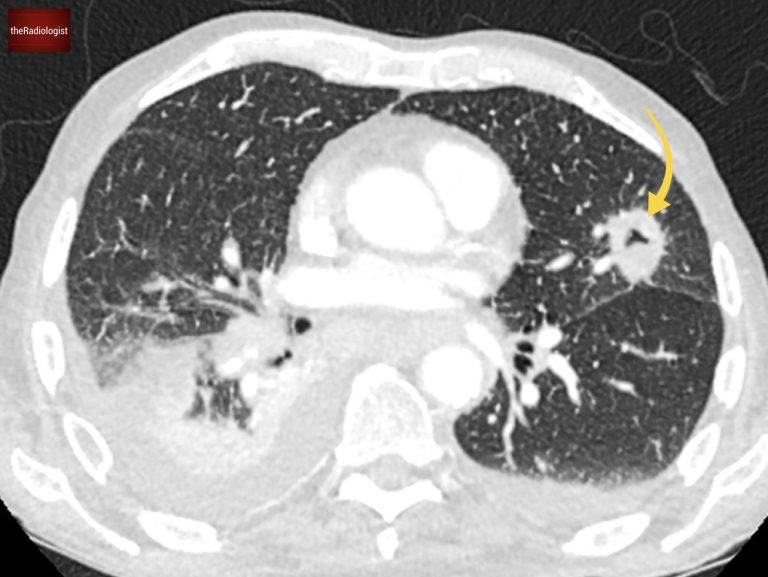

A post contrast CT scan was performed which confirmed the chest X-Ray findings of multiple cavitating lung lesions, enlarged mediastinal lymph nodes involving the aortopulmonary window as well as a bilateral pleural effusions.

The cavitating lesions are confirmed on CT.

On soft tissue windows we can see a right pleural effusion, left axillary node and enlarged mediastinal nodes. AP window nodes (arrow) are seen accounting for the X-Ray abnormality.